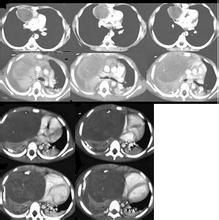

在前縱隔發現囊性腫物應想到胸腺囊腫的可能頸部胸腺囊腫可通過體格檢查發現縱隔內囊腫主要通過胸片檢查來發現CT掃描對於判斷胸腺囊腫的性質和囊腫的範圍有重要價值超音波檢查對胸腺囊腫的診斷也有幫助針吸活檢囊腫的壁上有胸腺組織即可確診。